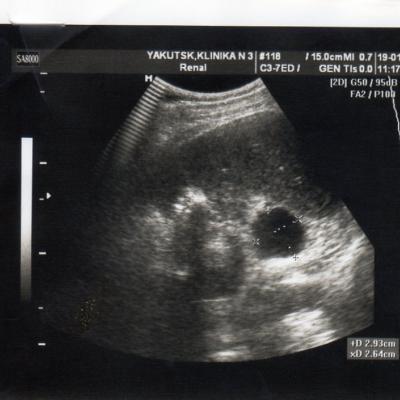

2 года назад у меня обнаружили кисту почки. в этом году УЗИ показала,что она исчезла. У меня одна единственная почка размером 146*71, увеличена. Киста размером 2,8*3,8 мм.сейчас почки болят.